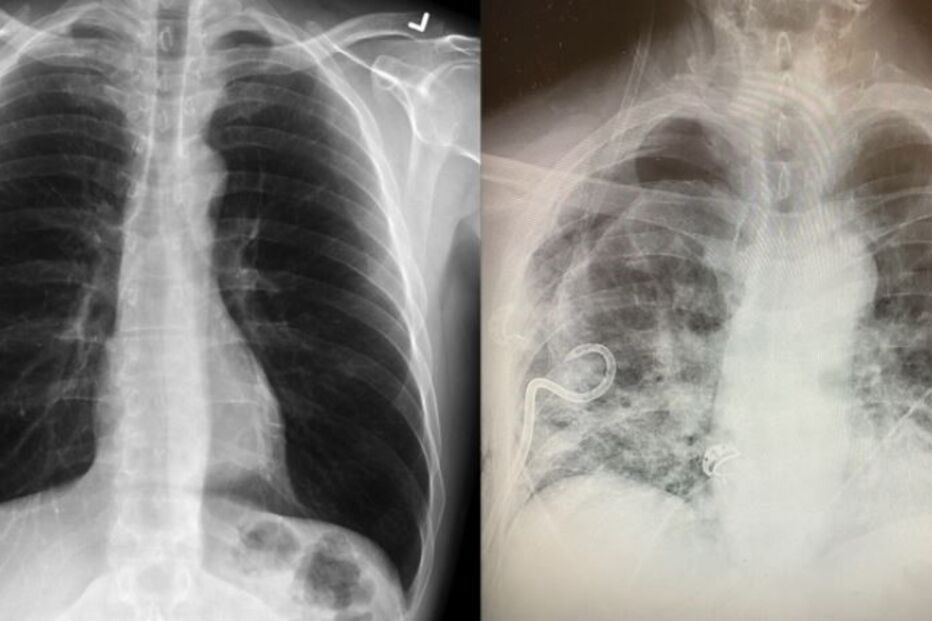

Uma médica da Universidade Tecnológica do Texas, nos Estados Unidos, divulgou imagens que usa para sustentar a tese de que que os pulmões de um infetado com Covid-19 ficam em pior estado do que os de uma pessoa fumadora.

A médica Bankhead-Kendall sublinha que os pulmões de uma pessoa infetada com Covid-19 são os "piores" do que qualquer outros que já tenha visto. "Mesmo pessoas que nunca tiveram tosse ou falta de ar, mas que testaram positivo para a Covid-19, há um, dois ou vários meses, apresentaram um raio-x ao tórax anormal", disse Bankhead-Kendall. Em alguns casos, os infetados apresentam coagulos nos pulmões ou estes entram mesmo em colapso.

A profissional diz que os pulmões de um infetado com o novo coronavírus podem tornar-se completamente, que explicam a falta de ar que entrou nos órgãos, e cheios de cicatrizes.